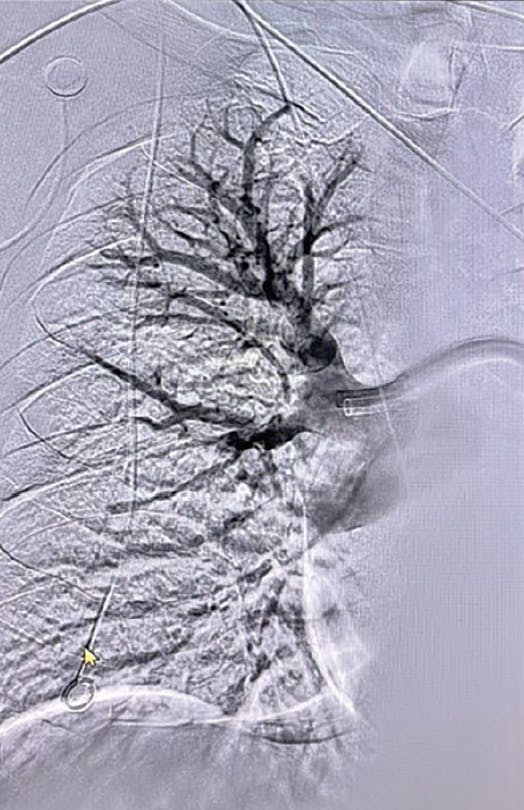

Figure 3. Post-thrombectomy lower right lobe angiogram.

Figure 4. Post-thrombectomy upper right lobe angiogram.

Figure 5. Post-thrombectomy left lobe angiogram.

Based on evaluation, we decided to pursue aspiration thrombectomy utilizing Lightning Flash through a 16-F, 65-cm Gore DrySeal sheath (Gore & Associates). We achieved access in the right femoral vein. The device time was 17 minutes, and the total procedure time was 30 minutes (Figure 3, Figure 4, Figure 5, and Figure 6). At the conclusion of the case, the total EBL was 175 mL, the patient had BP of 112/67 mm Hg, HR of 65 bpm, and oxygen saturation of 99% on 3 L nasal cannula.